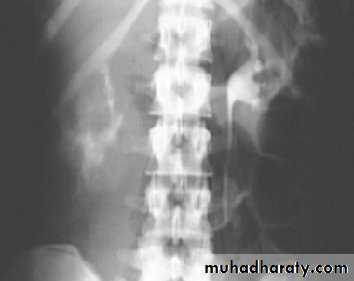

Horse shoe kidney -Kidneys may fail to separate.

-Almost invariably the lower poles remain fused.

-The kidneys axes are more parallel to the spine and malrotated.

-Diagnosis can be made by plain x-ray in some cases.

IVU shows

1. The kidneys at low position .

2.Close to the spine with long axis parallel to the spine .

3. Malrotation manifested by medially directed calyces.

4- The renal pelvis and ureters are anterior and lateral in position .